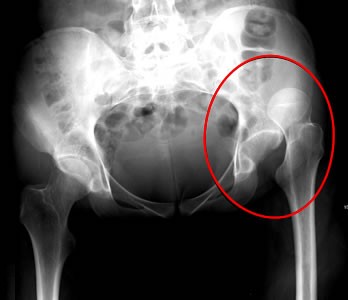

Image: John Heilman - Superior (Outward) Hip Dislocation

and English surgeon Richard Wiseman. A thigh dislocation is always perfect, that is, it cannot partially dislocate, due to the structure of the ball on the femur and the socket in the pelvic bone. Sea surgeon John Moyle reports "This is the hardest to set of all bones, and requires the greatest strength (and not a little skill) to reduce it."1

The idea of a thigh being dislocated 'inward' or 'outward' is hard to picture. Fortunately, a description of the signs of these types of dislocation makes them a little clearer.

If the Luxation be inwards, that Thigh appears longer than the other, and the Knee, Leg and Foot stands outwards, and a Tumor appears near the Perinæum [the region between the back of the sex organs and the anus]. If the Luxation be outwards, the signs are the Contrary, that Leg is shorter; near the Perinæum there is an hollowness, the Knee, Leg, and Foot, stand inwards, and the Heel cannot touch the ground, nor deck.5

In addition to the above-mentioned signs, Paré adds that in these dislocations you can feel the head of the femur in the groin and the patient will not be able to bend his leg towards his groin.6 This description (combined with the X-Ray image above) sounds a bit counter-intuitive. Since the leg is long in an inward hip dislocation, the femur has come out of its socket and gone downwards - why not call it an downward dislocation? And why not call the outward dislocation an upward dislocation? However, the name appears to have only to do with the direction in which the bone left the socket, not what happened as a result. Once loosed from the hip socket, the muscles pull the femur in one direction or another resulting in the symptoms described.